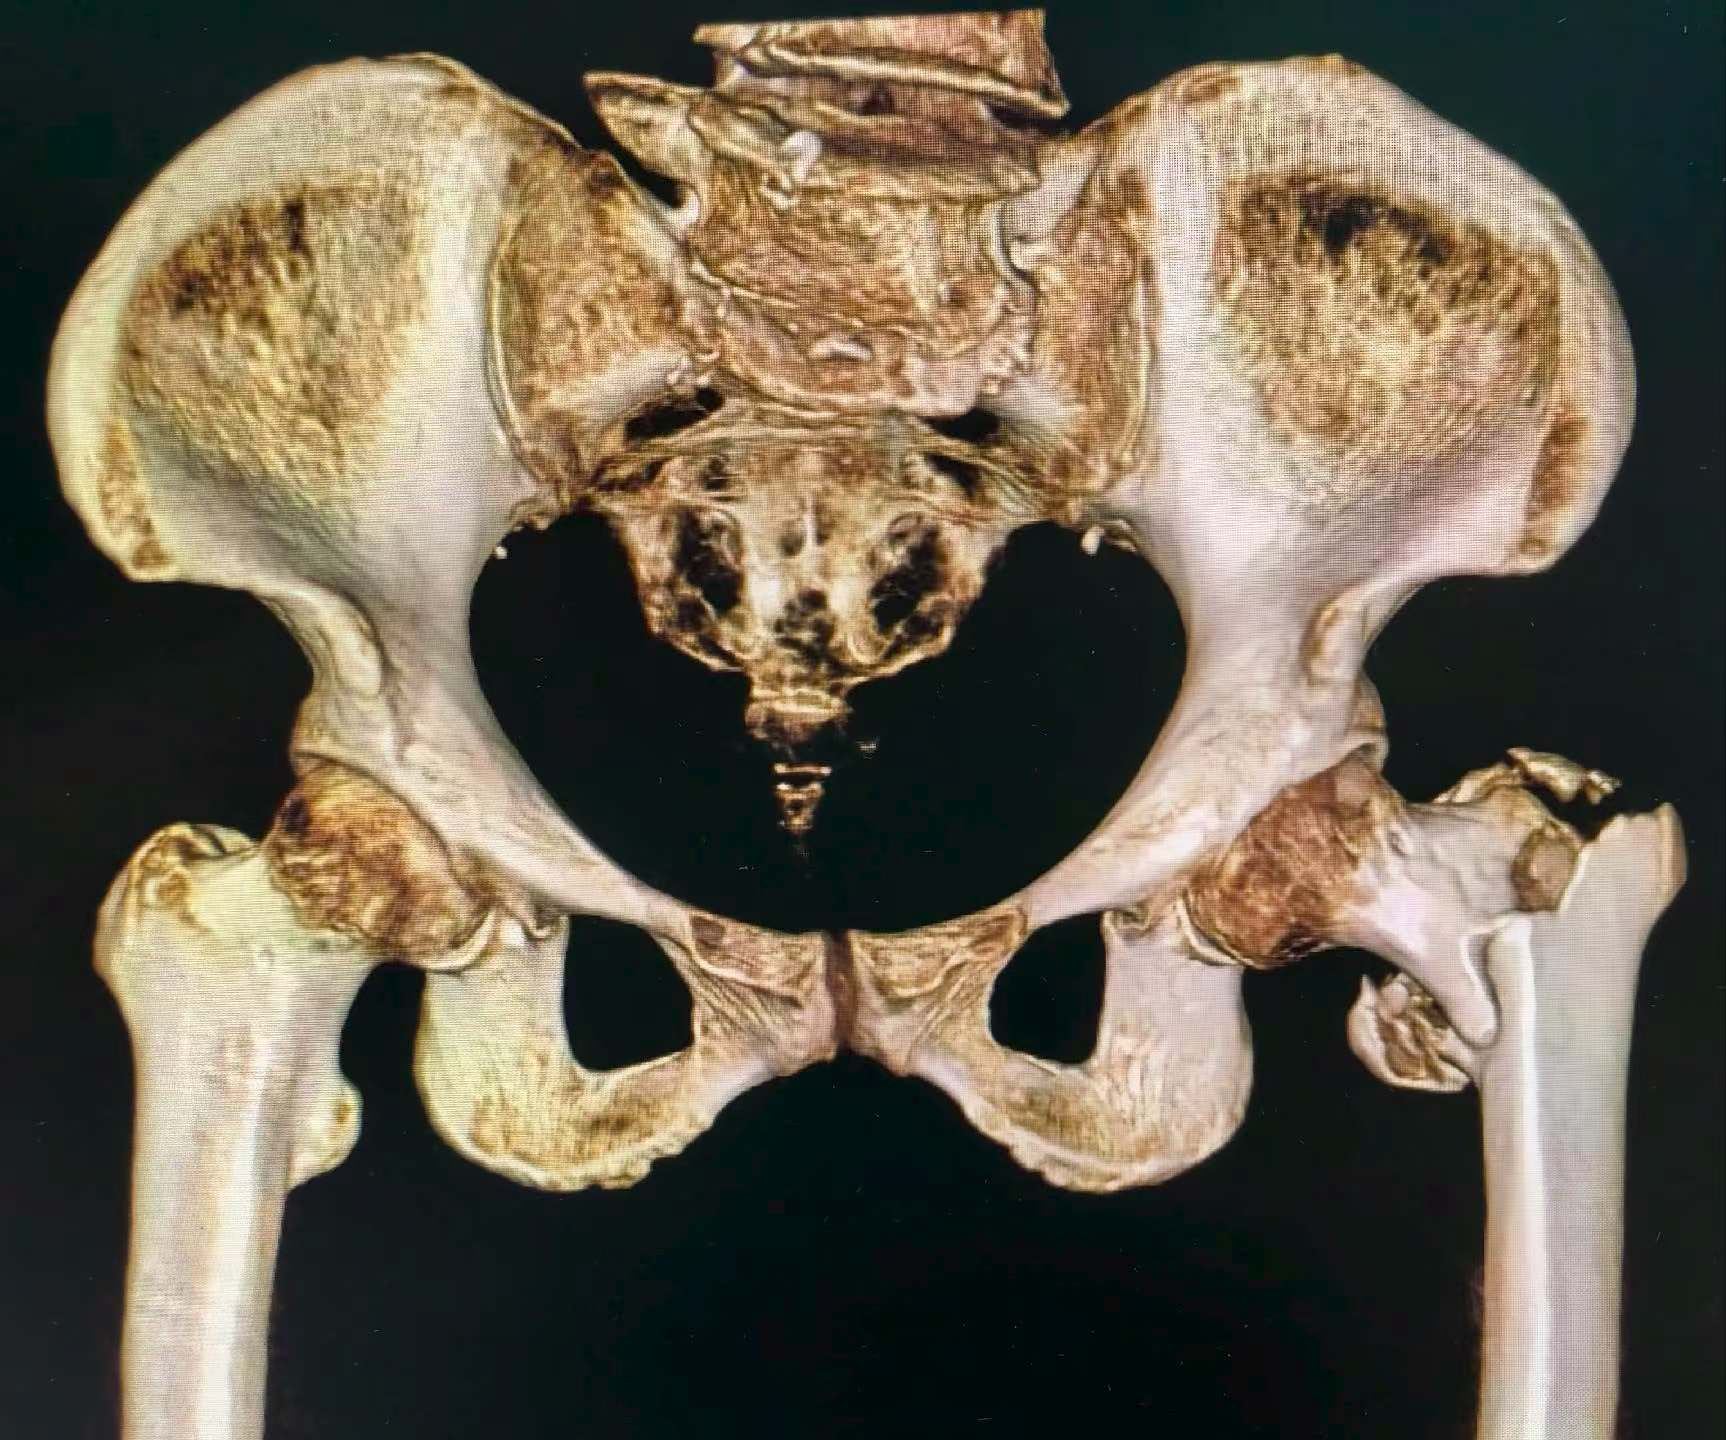

10月30日,骨关节科手术团队在C臂导航下实施“股骨转子间骨折闭合复位PFNA内固定术”——仅3个1厘米小切口,将一枚主钉经大转子顶点插入髓腔,再以螺旋刀片锁定,形成“三角稳定结构”。手术全程约20分钟,出血不足50毫升,最大幅度降低对患者的心肺影响。